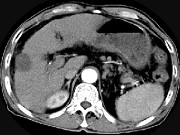

- 单项选择题男,63岁, 肝区疼痛不适1个月,皮肤巩膜无黄染, AFP高于正常,CT所见如图, 最可能的诊断为 ( )